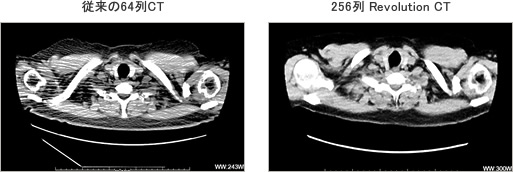

特長〈2〉放射線量が少なくても高画質

256列Revolution CTには少ない放射線量でも高品質の画像を得ることができる機能があります。同じ少ない放射線量で画像を比較した場合、従来の64列CTより256列Revolution CTの方が、きれいな画像を得ることができます。